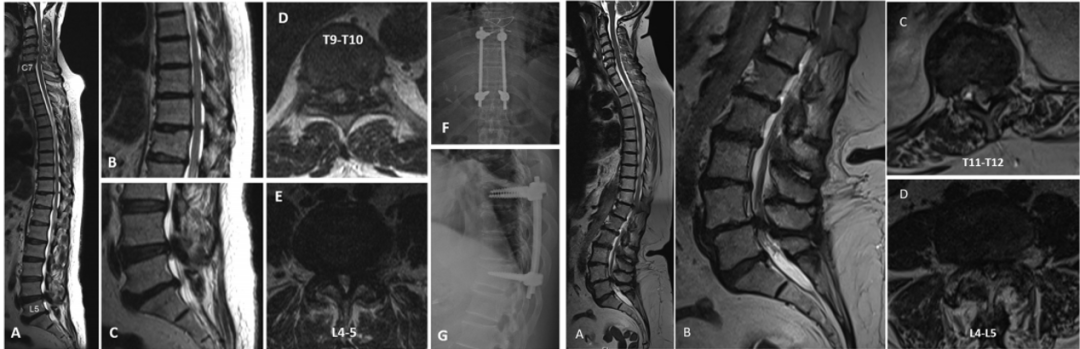

D型:颈胸腰,在所有3个区域都有狭窄,其中一个或多个区域有症状。

D型以上肢为主的脊髓病和间歇性跛行患者7例,首先接受颈椎减压,然后进行胸椎和腰椎节段减压,两次手术之间的平均间隔为12.2个月;3例软骨发育不全患者患有脊柱的整体狭窄,2例因寰枢椎不稳在颅颈交界处接受了减压融合术,在2年随访中没有出现明显的胸髓病或神经源性跛行症状。另1例以下肢神经功能障碍为主,接受单次胸腰椎减压治疗;7例有明显腰椎管狭窄的患者接受了分阶段的颈椎和胸椎减压,平均手术间隔为3.2个月,在2年随访中也没有出现神经源性跛行症状。